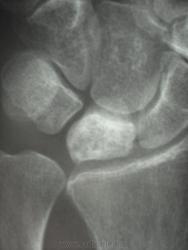

женщина, 1956 года рождения, жалобы на боли в правой лучезапястном суставе в течение полу года, травму отрицает. Кроме остеохондропатии полулунной кости в голову ничего не приходит. Ваше мнение коллеги))))))))

Скоро наступит патологический перелом...

Остеохондропатия - удел детского возраста. Здесь, думаю, правильнее говорить об асептическом некрозе.

Остеохондропатия (греч. οστεοχονδροπαθια) – асептический некроз губчатой кости, протекающий хронически и дающий осложнения в виде микропереломов. Остеохондропатии являются следствием местных расстройств кровообращения, возникающих в результате воздействия различных факторов: врождённых, обменных, травматических и др.